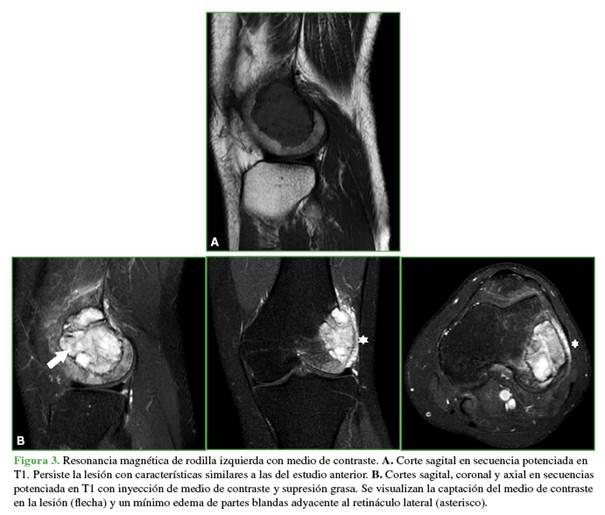

La resonancia magnética con medio de contraste sirvió para definir la lesión y el proceso inflamatorio en las partes blandas (Figura 3).

En la resonancia magnética, las imágenes en secuencias potenciadas en T1muestran una intensidad de señal de baja a intermedia, no homogénea. En secuencias sensibles a líquidos, la intensidad de señal es alta, no homogénea. Tras la inyección del medio de contraste, se puede ver un realce heterogéneo.